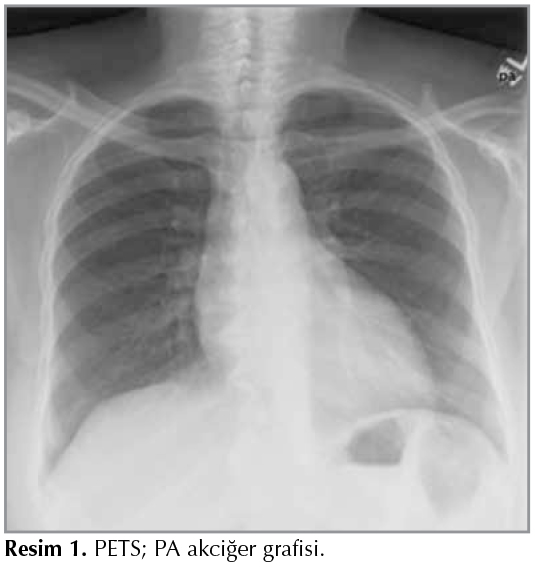

Tanının ikinci aşaması g?r?nt?lemedir. En basit g?r?nt?leme y?ntemi PA akciğer grafisidir (Resim 1). PA akciğer grafisi genelde normal saptanmakla birlikte, trakea l?menine ait hiperl?sen alanda d?zensizlik g?r?lebilir (Resim 2).

Resim 1